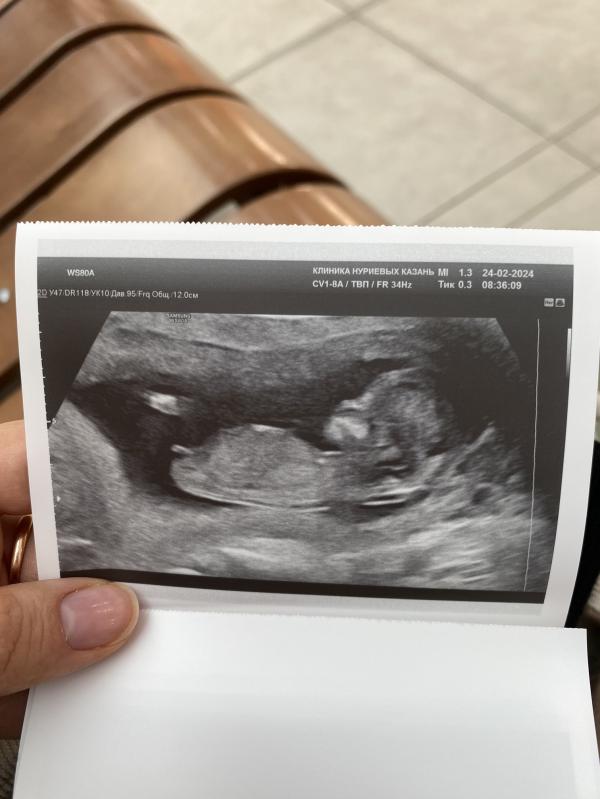

Сегодня был первый скрининг 🙏🏻

По показателям все в норме .

ПДР 3 сентября поставили 😂

Ходили с мужем , такая милота, малыш там ручками машет , ножками дрыгает ☺️

Так интересно кто там 👧🏻 👦🏻

Думаю, что 98% девочка)) половой бугорок под таким углом, как у девочек)

Мне тоже кажется девочка, бугорок вниз 🙈